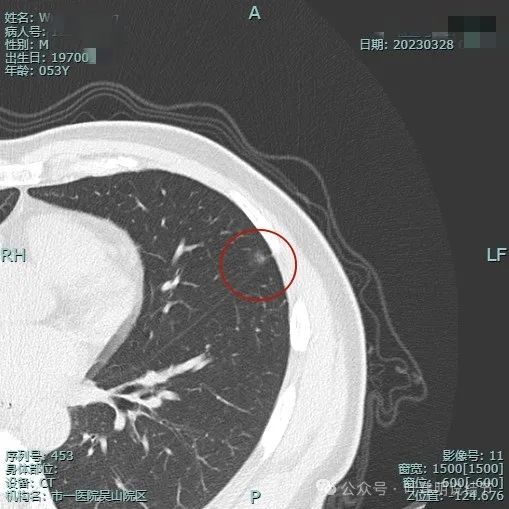

2023年3月影像展示:

病灶出现,密度淡,靠叶间裂较近,整体轮廓较为清楚。

密度纯,但不是太均匀,感觉稍不均,瘤肺边界清,贴胸膜近。

与叶间裂也是贴着的。

靶重建后见病灶密度不是很淡,轮廓较清,离叶间裂近但未见明显牵拉。

上图层面病灶贴着叶间裂,轮廓与瘤肺边界清楚,表面不光滑。

上图显得瘤肺边界稍模糊。

病灶似有极微细血管进入,贴着叶间胸膜但没有牵拉或明显凹陷。